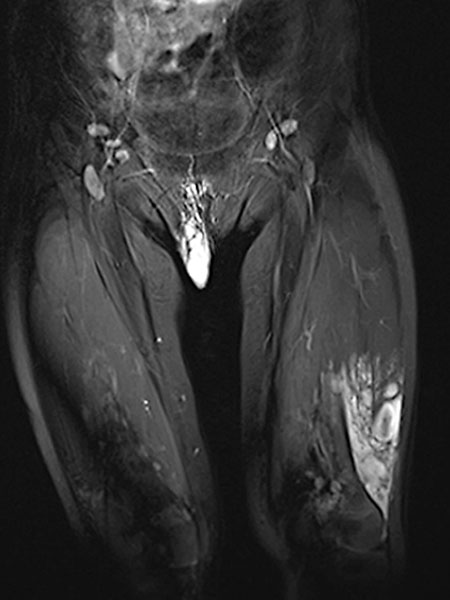

In der koronaren, T2-gewichteten, fettunterdrückten MRT im 32. Lebensmonat findet sich das charakteristische, stark hyperintense = weiße Signal einer Slow-flow-Gefäßmalformation in der labialen Läsion. Zudem auch ähnlich stark hyperintenses Signal in einer intramuskulären Läsion im Musculus vastus lateralis des linken Oberschenkels. Damit ist eine Gefäßmalformation sehr wahrscheinlich.

In der Spätphase der dynamischen, zeitlich hochaufgelösten, kontrastmittelunterstützten MR-Angiographie 135 Sekunden nach i. v. Kontrastmittelapplikation kommt es zu einem langsamen, verzögerten Kontrastmittelpooling in der Läsion. Eine arteriovenöse Malformation mit ihrem schnellen Durchfluss kann somit klar ausgeschlossen werden. Ebenfalls langsame Anreicherung der zweiten Läsion am lateralen distalen linken Oberschenkel.